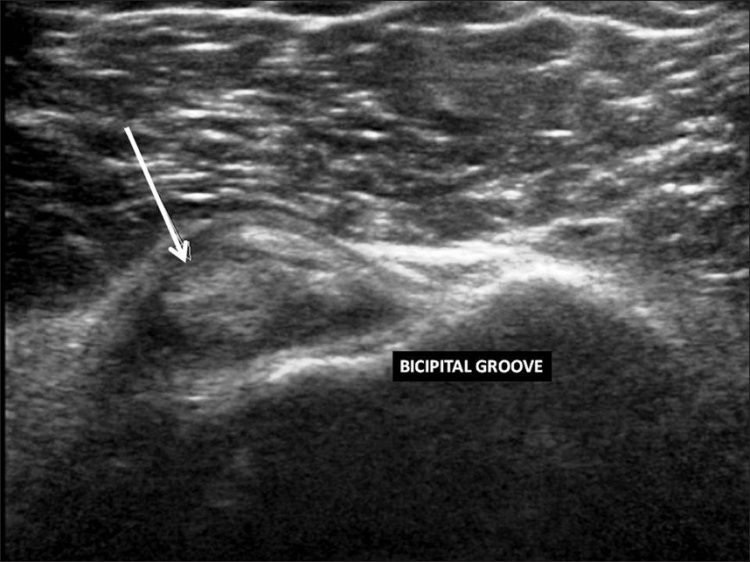

La ecografía del hombro comienza examinando el surco bicipital (BG) y la cabeza larga del tendón del bíceps braquial. El paciente está sentado frente al operador en una posición neutra, su mano colocada con la palma hacia arriba sobre el muslo. Se realiza una imagen de eje corto colocando el transductor sobre la metáfisis humeral proximal perpendicular al húmero. La imagen del eje largo del tendón se obtiene girando el transductor a una posición paralela a la diáfisis humeral [Figura 1]. Luego, se examina el tendón del subescapular. El brazo del paciente se fija sobre el flanco y el antebrazo se abduce en rotación externa. Se realizan vistas de eje largo y corto del tendón [Figura 2]. Los tendones infraespinoso y redondo menor se examinan desde una vista posterior del hombro. El paciente se gira 90°, su mano se coloca sobre el hombro opuesto y el transductor se orienta en el plano axial sobre la cabeza del húmero [Figura 3]. La articulación glenohumeral y la escotadura espinoglenoidea también se examinan en una vista posterior del hombro. El transductor ahora se mueve medial y caudalmente en el plano transversal hasta que se vea el margen posterior de la articulación glenohumeral y luego, más medialmente para mostrar la escotadura espinoglenoidea [Figura 4]. El tendón supraespinoso se escanea en una vista anterior del hombro. El paciente está sentado frente al operador. El brazo del paciente se coloca en una posición posterior, la mano dorsal en el ala ilíaca opuesta o la mano palmar en el ala ilíaca ipsilateral. Se obtienen vistas de eje largo y corto del tendón supraespinoso. Luego se realiza la exploración del manguito de los rotadores durante las maniobras dinámicas. El transductor se coloca sobre el acromion. El brazo del paciente se abduce con el codo flexionado a 90° o/y el brazo se extiende anteriormente [Figura 5]. Finalmente, se escanea la articulación acromioclavicular. La mano del paciente se coloca con la palma hacia arriba sobre el muslo. El transductor se coloca sobre la parte superior del hombro en un plano coronal [Figura 6].

Derrame de la articulación gleno-humeral [Figura 17], derrame de la bursa subacromial-subdeltoidea [Figura 18], bursitis calcificante [Figura 19], artropatías y dislocaciones de la articulación acromioclavicular [Figura 20], rotura del tendón del bíceps [Figura 21], sinovitis [Figura 22] y la luxación [Figura 23] son las principales patologías no relacionadas con el manguito rotador que se observan en la ecografía de hombro [Tabla 3]. [8-9] La ecografía es sensible para la detección de derrame de la articulación glenohumeral y derrame bursal subdeltoideo subacromial, incluso en pequeñas cantidades. La aspiración de líquido bajo guía ecográfica permite un diagnóstico preciso. La penetración intrabursal de depósitos calcificados en el tendón provoca una bursitis microcristalina aguda y dolorosa. La subluxación o dislocación de la articulación acromioclavicular aparece como un ensanchamiento de la cavidad articular y un abultamiento de la cápsula superior y el ligamento. La rotura de la cabeza larga del tendón del bíceps braquial suele generar un bulto en la parte anterior del brazo, conocido como "signo de Popeye". La rotura del tendón suele ocurrir a nivel intrarticular con retracción distal, dejando un surco vacío. En los desgarros agudos, el muñón del tendón aparece rodeado de líquido. La luxación del tendón del bíceps medial se diagnostica con ecografías transversales, que muestran el surco bicipital y el tendón que recubre la tuberosidad menor.#dieciséis#